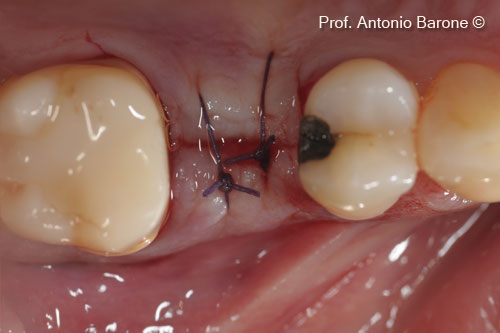

Hình ảnh lâm sàn của các đường khâu